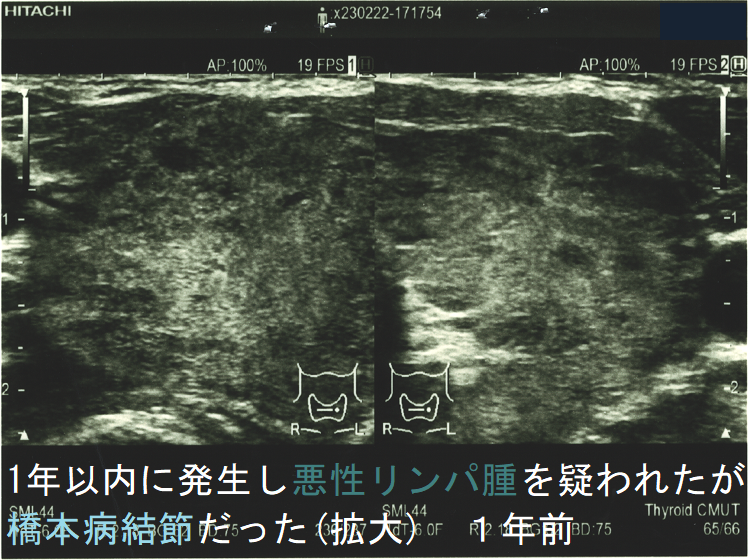

![1年以内に現れ悪性リンパ腫が疑われたが橋本病結節だった 1年前 (水平断)[拡大] 1年以内に現れ悪性リンパ腫が疑われたが橋本病結節だった 1年前 (水平断)[拡大]](../images/special/thyroid2/images20251130213537.png)